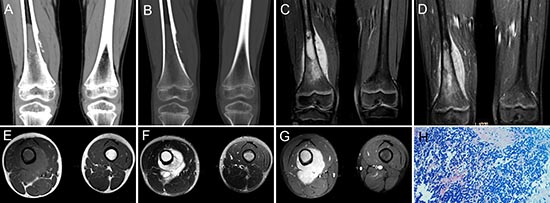

Figure 7: pPNET in a 9-year-old boy. Precontrast CT images showed bony destruction in the right distal femur with irregular iso-dense masses in the marrow cavity and cortex (A and B). Precontrast MRI showed the irregular mass was hypo-intense on T1WI (C and E) and hyper-intense on T2WI (F). Contrast MRI showed the mass had significant enhancement (D and G). (H & E) staining (H × 100) showed the tumor tissue consisted of poorly differentiated small round cells.

Figure 4: pPNET in a 20-year-old woman. Precontrast MRI showed a lobulated soft tissue mass in the right neck that was iso-intense on T1WI (A) and hyper-intense on T2WI (B). Contrast MRI showed the mass had significant and heterogeneous enhancement (C). Enhanced coronal MRI (D) showed a mass with poorly defined margins. Precontrast CT images showed a large low-density mass with a well demarcated margin (E). Bone windows showed destruction of the right vertebrae (F). Contrast CT images showed the mass had slight heterogeneous enhancement (G). The poorly differentiated small round tumor cells were CD99 positive (H × 100).